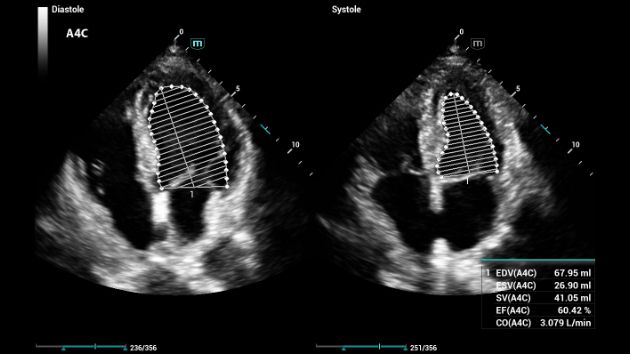

Auto EF

Maggiore produttività con il calcolo automatico

Auto EF è un modo intelligente per analizzare le ecografie 2D e riconoscere automaticamente fotogrammi diastolici/sistolici nonché generare una serie di misurazioni, come EDV/ESV/EF, per valutare la funzione del ventricolo sinistro per una maggiore produttività.

Consona Series Cardiovascular Solution - AutoEF feature clinical image